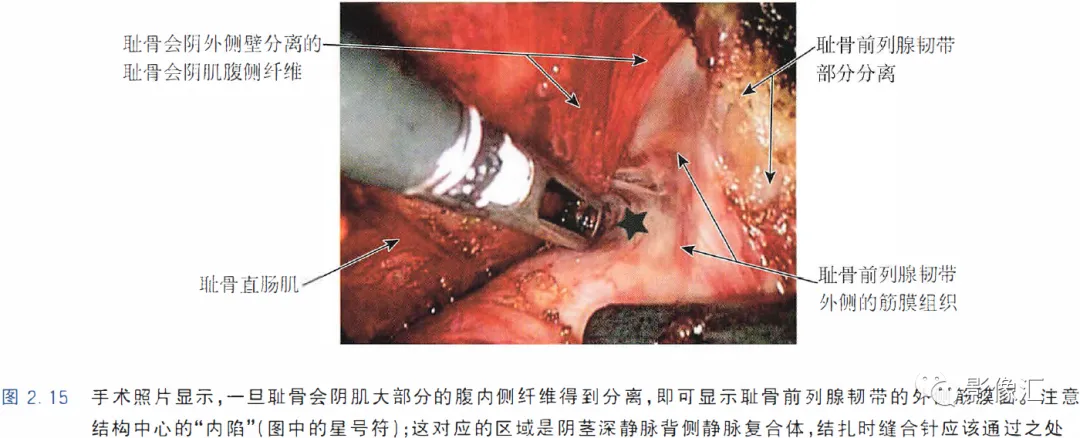

肛提肌与尿失禁的外在因素(主动因素)相关。肛提肌由两个肌肉平面组成,即耻尾肌和髂尾肌。耻尾肌起源于耻骨的中分支(mid-branch of the pubis),在肛尾韧带和尾骨的水平从背侧插入。耻尾肌的内侧纤维向内走行,在肛门直肠管的水平处构成肛门外括约肌后面的环,让直肠形成一定弯曲,有助于肛门压力和闭合机制。同时,耻骨直肠肌的内侧纤维向尾部中线移动,在尿道膜部以及前列腺尖部及其括约肌系统外侧走行,并在会阴体、肛门外括约肌的最深部分和尿道球部水平插入。这些肌肉纤维被称为耻骨会阴肌(也称为耻骨尿道肌或前列腺提肌)。耻骨会阴肌构成会阴底部的腹内侧部分,并且最终可以覆盖耻骨前列腺韧带的外侧表面,使得其更远端的纤维沿着平行于尿道膜部的平面走行。在大多数情况下,要完整保留这个肌肉平面。要求部分分离耻骨前列腺韧带,目的是可以找到正确的解剖平面进行手术切除(图2. 15)。MRI在评估前列腺尖部、尿道膜部和尿道括约肌复合体中的作用